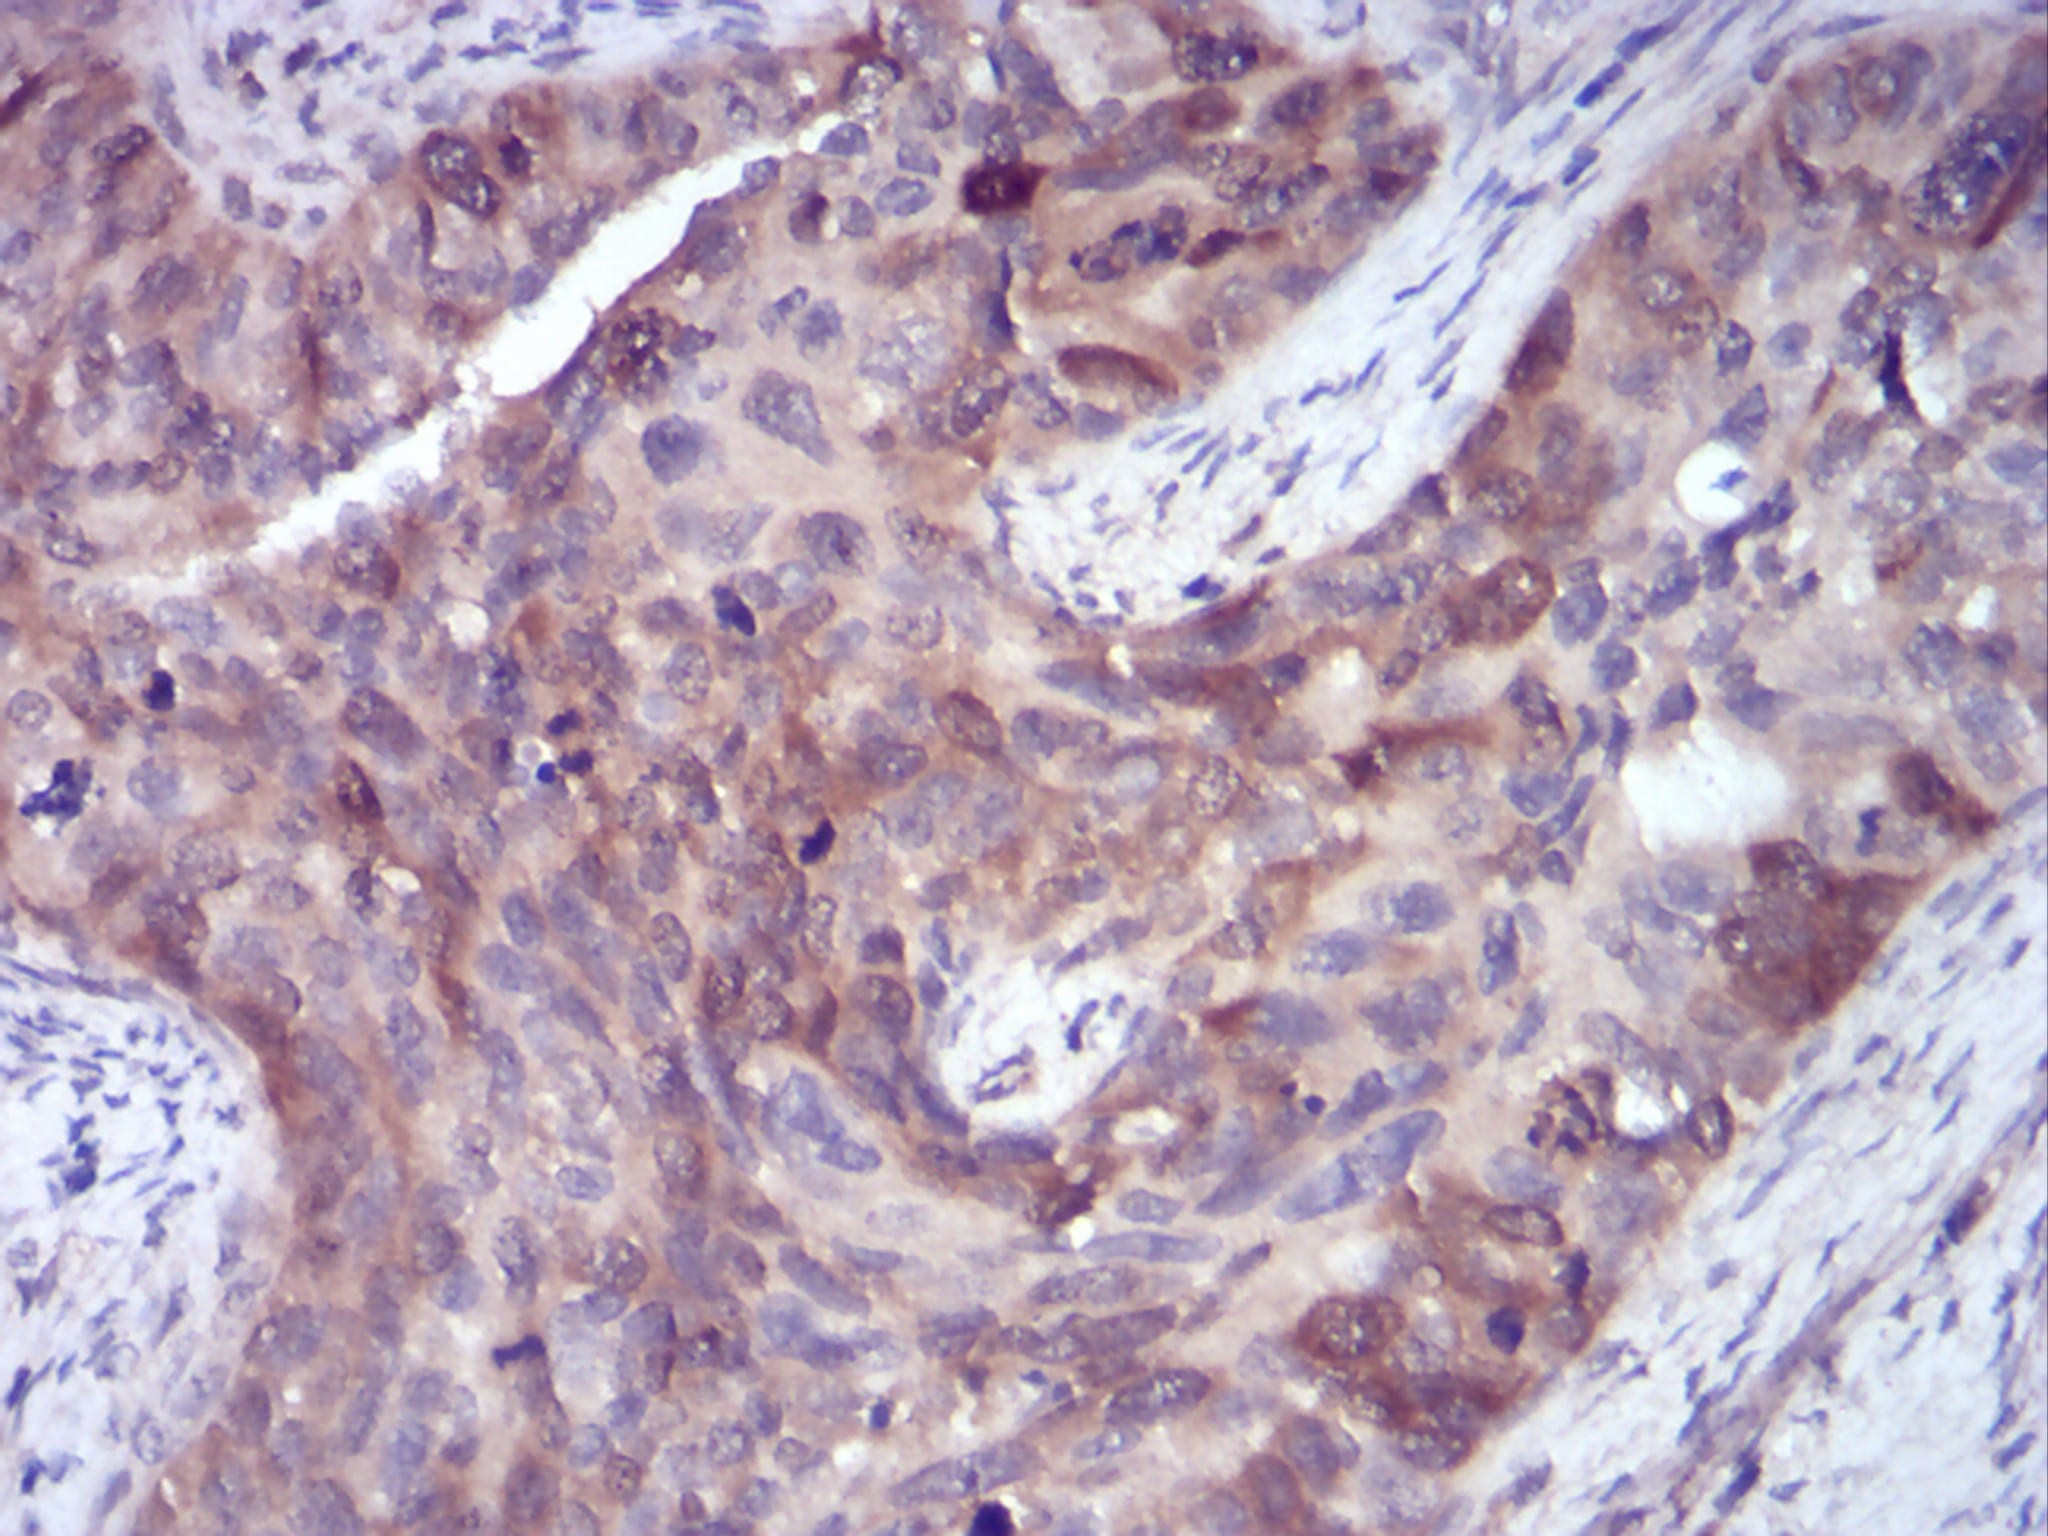

- Immunohistochemical analysis of paraffin-embedded human cervical cancer tissues using SELL mouse mAb with DAB staining.

- Immunohistochemical analysis of paraffin-embedded human ovarian cancer tissues using SELL mouse mAb with DAB staining.